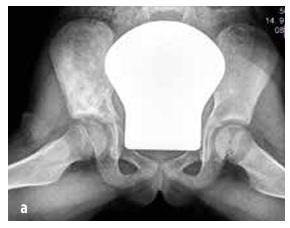

Malignant tumours

In children, the most common types are osteosarcoma (55%, see Figure 5) and Ewing’s sarcoma (35%, see Figure 6), while chondrosarcoma is extremely rare. This group also includes soft tissue sarcomas (rhabdomyosarcoma and non-rhabdomyosarcomas), mesenchymal cell tumours, extraskeletal Ewing’s sarcoma, synovial sarcoma, fibrosarcoma and embryonic sarcoma.

Figure 6

Ewing’s sarcoma affecting the pelvic skeleton